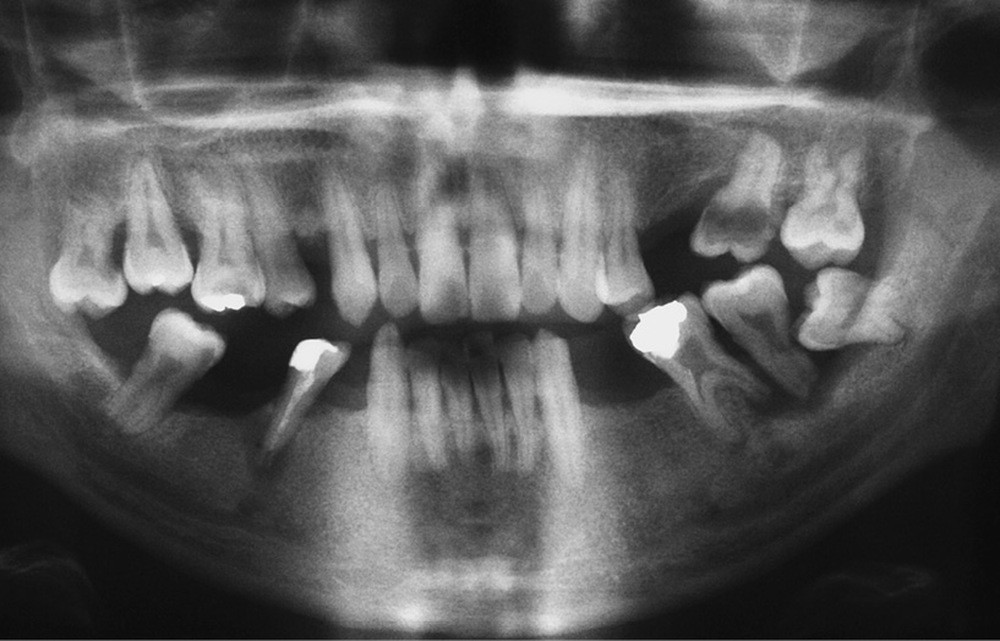

L’obésité, définie par un indice de masse corporelle (IMC) ≥ 30 kg/m2, est une maladie inflammatoire chronique complexe et multifactorielle caractérisée par un dépôt excessif de graisse dans le tissu adipeux. Selon l’OMS, depuis 1975, le nombre de cas d’obésité a presque triplé à l’échelle planétaire [1]. En 2020, près d’un Français sur deux était en surpoids, tandis que 17 % étaient obèses [2]. Or l’obésité est responsable d’une haute mortalité à l’échelle mondiale et est un facteur de risque majeur pour de nombreuses maladies, dont les maladies cardiovasculaires, le diabète de type 2 et certains cancers [1]. Son impact sur la santé des populations et son coût économique et social sont donc considérables. Ces deux dernières décennies, de nombreuses études ont montré que l’obésité pouvait aussi être incriminée dans la détérioration de la santé bucco-dentaire [3] (fig. 1 à 7).